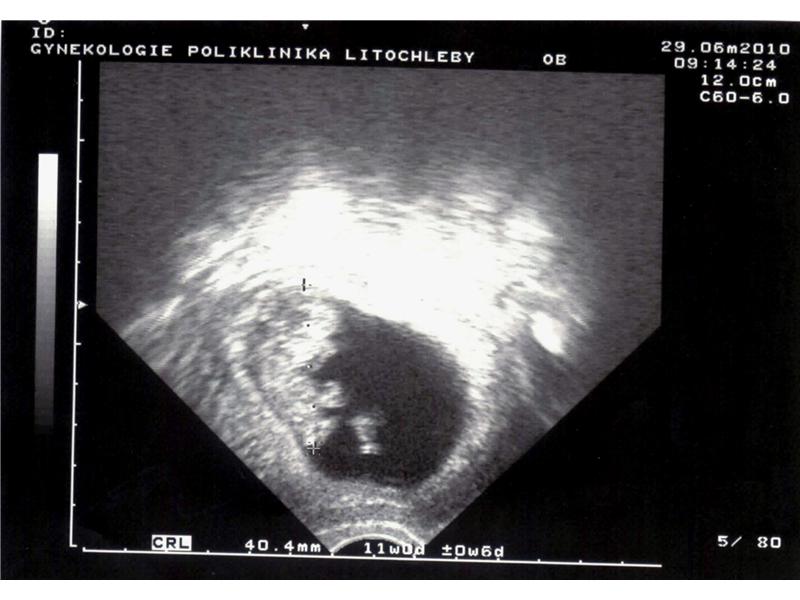

Zdroj: archiv redakce

2 / 2